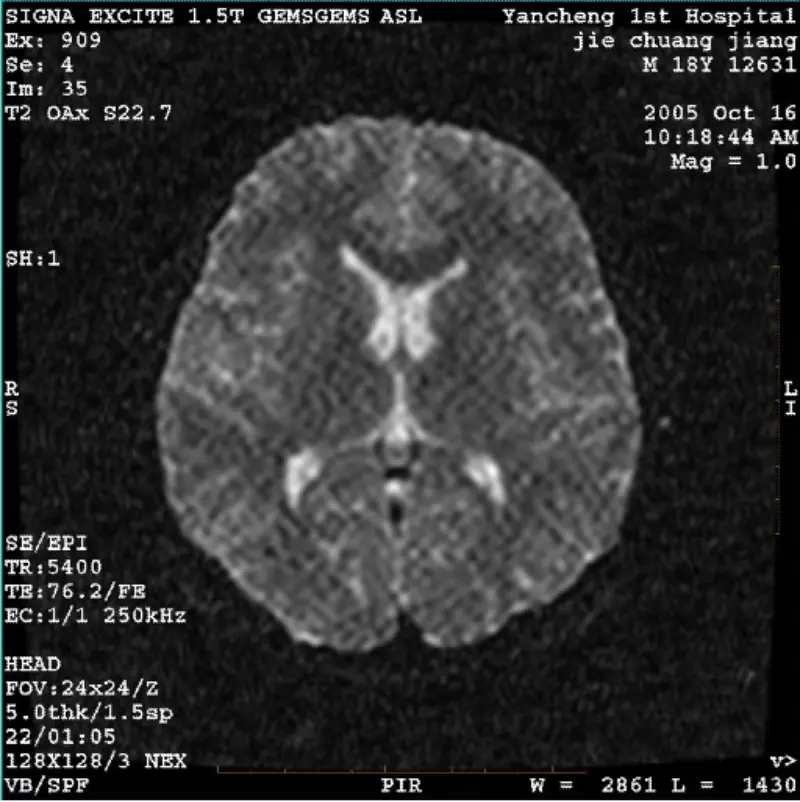

อ่านเพิ่มเติมระบบ: MR 0.35T การโอเวชั่น โรงพยาบาล: โรงพยาบาลทั่วไป Daqing Oilfield ปัญหา/อาการ รูปภาพของโปรโตคอล FRFSE และ GRE มีโกสต์และบางครั้งระบบ SNR ต่ำ: MR 0.35T Ovation โรงพยาบาล: โรงพยาบาลทั่วไป Daqing Oilfield ปัญหา/อาการ รูปภาพของโปรโตคอล FRFSE และ GRE มีรูปภาพโกสต์และบางครั้งรูปภาพ SNR ต่ำ......